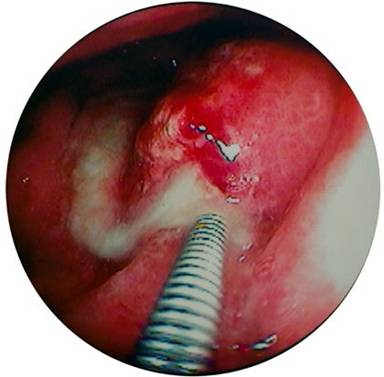

A seventy two-years old male presented with fever, abdominal discomfort and vomiting six weeks after an episode of gall stone acute pancreatitis. An i.v. contrast abdominal Ct scan revealed a cystic collection 6x7 cm with air level at the tail of pancreas bulging towards stomach. Lab exams revealed only leukocytosis. On gastroscopy a small fistulous opening was found at the posterior wall of upper stomach corpus. A pus like discharge from the opening was noted (Figure 1). Further, the fistulous opening was step-wise dilated so that the instrument tip carefully entered the cavity (Figure 2). The cavity was full of debris, semi-solid necrotic material and a greenish liquid. Culture sample and cytology were both negative. The debris was aspirated through the scope meticulously. Further, the cavity was thoroughly irrigated with sterile normal saline and a nasobiliary catheter was left inside to secure a continuous irrigation along with drainage. The patient was kept on nil by mouth, i.v. broad spectrum antibiotics and gradually recovered uneventfully. White blood cells returned to normal and an i.v. contrast CT scan two months later depicted no fluid collections.

Figure 1. Intra-gastric fistula with pus exudate. |